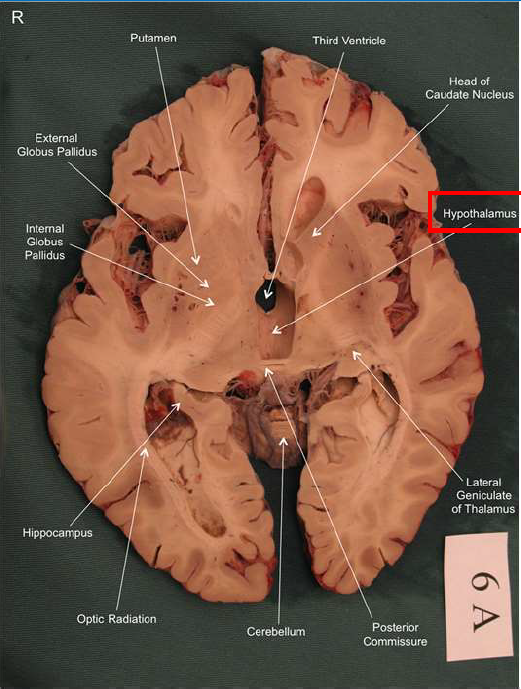

What is this?

hippocampal fornix